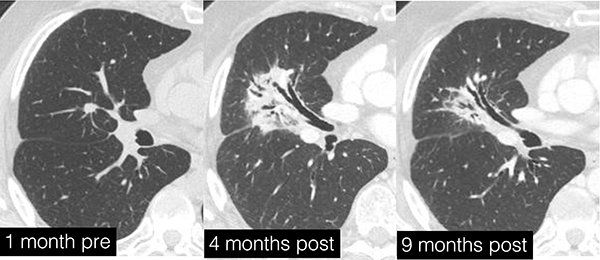

The treatment for lung cancer with the “Cyber Knife” (thoracic stereotactic body radiation therapy) went well, but six months later the patient notices something wrong with her breathing, and a new round of imaging shows a growing mass at the tumor site. Instead of cancer recurrence, close examination of the new imaging studies show that the mass is acute radiation pneumonitis, characterized by acutely inflamed tissue around the treatment site.

Kimberly Kallianos, MD, presented her findings on oncologic therapy-induced lung disease at the RSNA 2024 annual meeting. She explained that acute radiation pneumonitis and the associated chronic fibrosis in the lungs can manifest six to 12 months after SBRT treatment and can evolve for about one year. This condition, though distressing, can often be resolved or improved with steroid treatment.